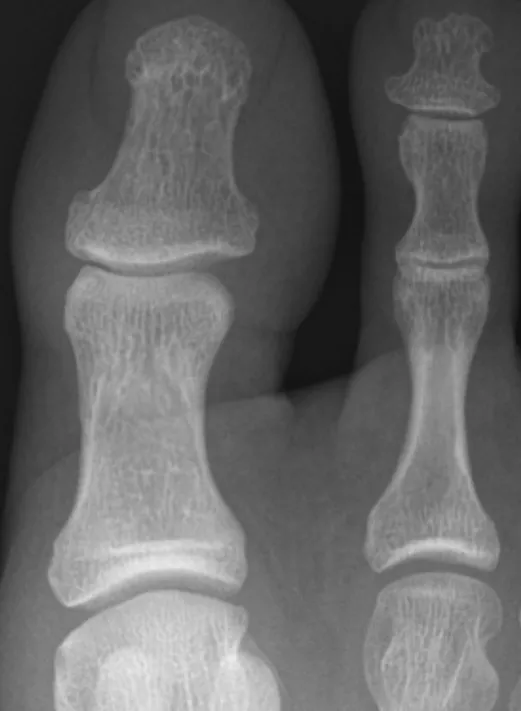

身体診察ではBMI 23、図1に左足の所見と両足の単純X線(図2)を示す。肘関節伸側に軽度の鱗屑を伴う丘疹を認めた。

図1 診察時

左足第1指IP関節周囲から

その末梢にかけて腫脹と発赤

爪甲剥離症